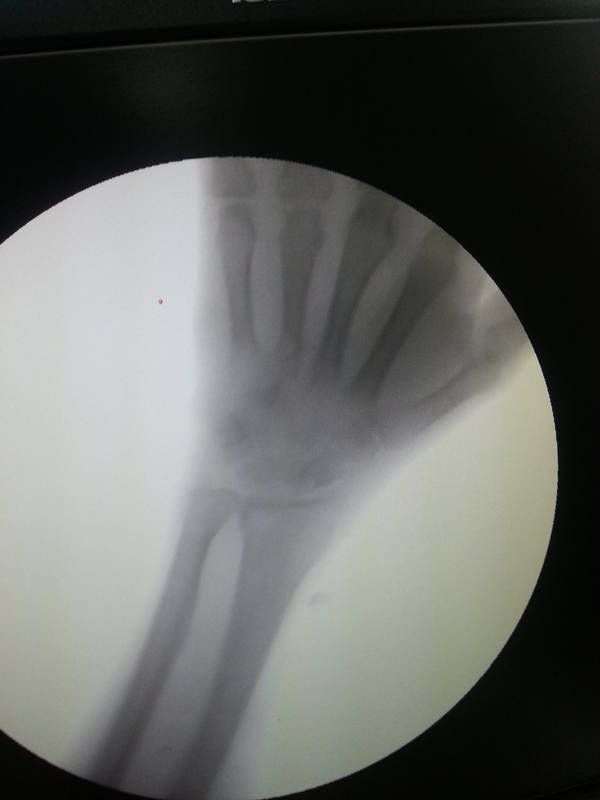

感谢手外科网以及手足显微外科论坛的老师们,今天这个病人我给予扩大清创,原来第4掌骨位置愈合良好,骨髓腔打开未见脓性分泌物。但是第头状骨感染严重,给予摘除整个头状骨。以下是摘除的死骨和C臂透视的结果。 20151230_105513.jpg 20151230_115344.jpg

伙计,今天给予臂丛麻醉下扩大清创,原来骨折的位置愈合良好。但是头状骨位置骨感染严重,给予摘除死骨。估计是整个头状骨都摘除了。